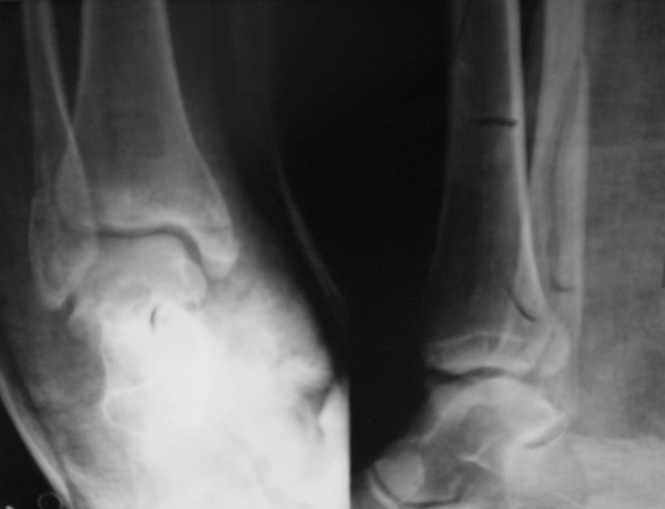

Стандартными снимками считается прямая, боковая и мортиз!!!, а так трудно гадать, насколько потеря длины малоберцовой. На боковом снимке не сопоставленный перелом медиальной лодыжки и перелом заднего края без смещения.

In this case we say about three malleolar fracture of ankle.Moreover lateral malleolus have external rotation displacement.Becouse this great suprise to me question - what kind of treatment.Of course open reduction with internal

fixation.

Ув. коллеги. Мы считаем, что синтезировать необходимо медиальную лодыжку, она ротирована. Малоберцовую кость лучше не трогать. Довольно травматично будет, фрагменты неплохо стоят. И то, оперировать медиальную лодыжку где-то в трехнедельном сроке, чтобы малоберцовую кость не развалить. Мнений много, мы благодарны за участие.

Очень жаль, что Вы так считаете и не прислушались к мнениям уважаемых коллег. Проблема этого голеностопного сустава не в "висячей" внутренней лодыжки, а ротированной и, возможно, укороченной малоберцовой кости. На снимках подвывиха как-буд-то бы нет, но таран ротирован и это в дольнейшем будет причиной раннего артроза.